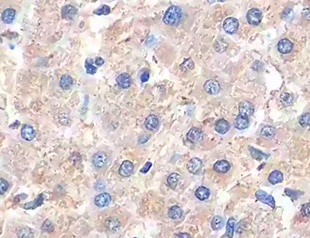

View Larger

PGC1 alpha in Human Liver Cancer. PGC1 alpha was detected in immersion fixed paraffin-embedded sections of human liver cancer tissue using Mouse Anti-Human PGC1 alpha Monoclonal Antibody (Catalog # MAB10784) at 5 µg/mL for 1 hour at room temperature followed by incubation with the Anti-Mouse IgG VisUCyte™ HRP Polymer Antibody (VC001). Before incubation with the primary antibody, tissue was subjected to heat-induced epitope retrieval using Antigen Retrieval Reagent-Basic (CTS013). Tissue was stained using DAB (brown) and counterstained with hematoxylin (blue). Specific staining was localized to nuclei in hepatocytes. Staining was performed using our protocol for IHC Staining with VisUCyte HRP Polymer Detection Reagents.